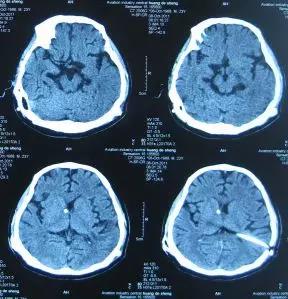

头部CT(外院2011年10月3日)示V-P分流术后,右侧额叶及左侧顶叶见片状低密度影;第三脑室、双侧脑室扩张;中线略向右移位(图-6)。

图-6:2011年10月3日头部CT